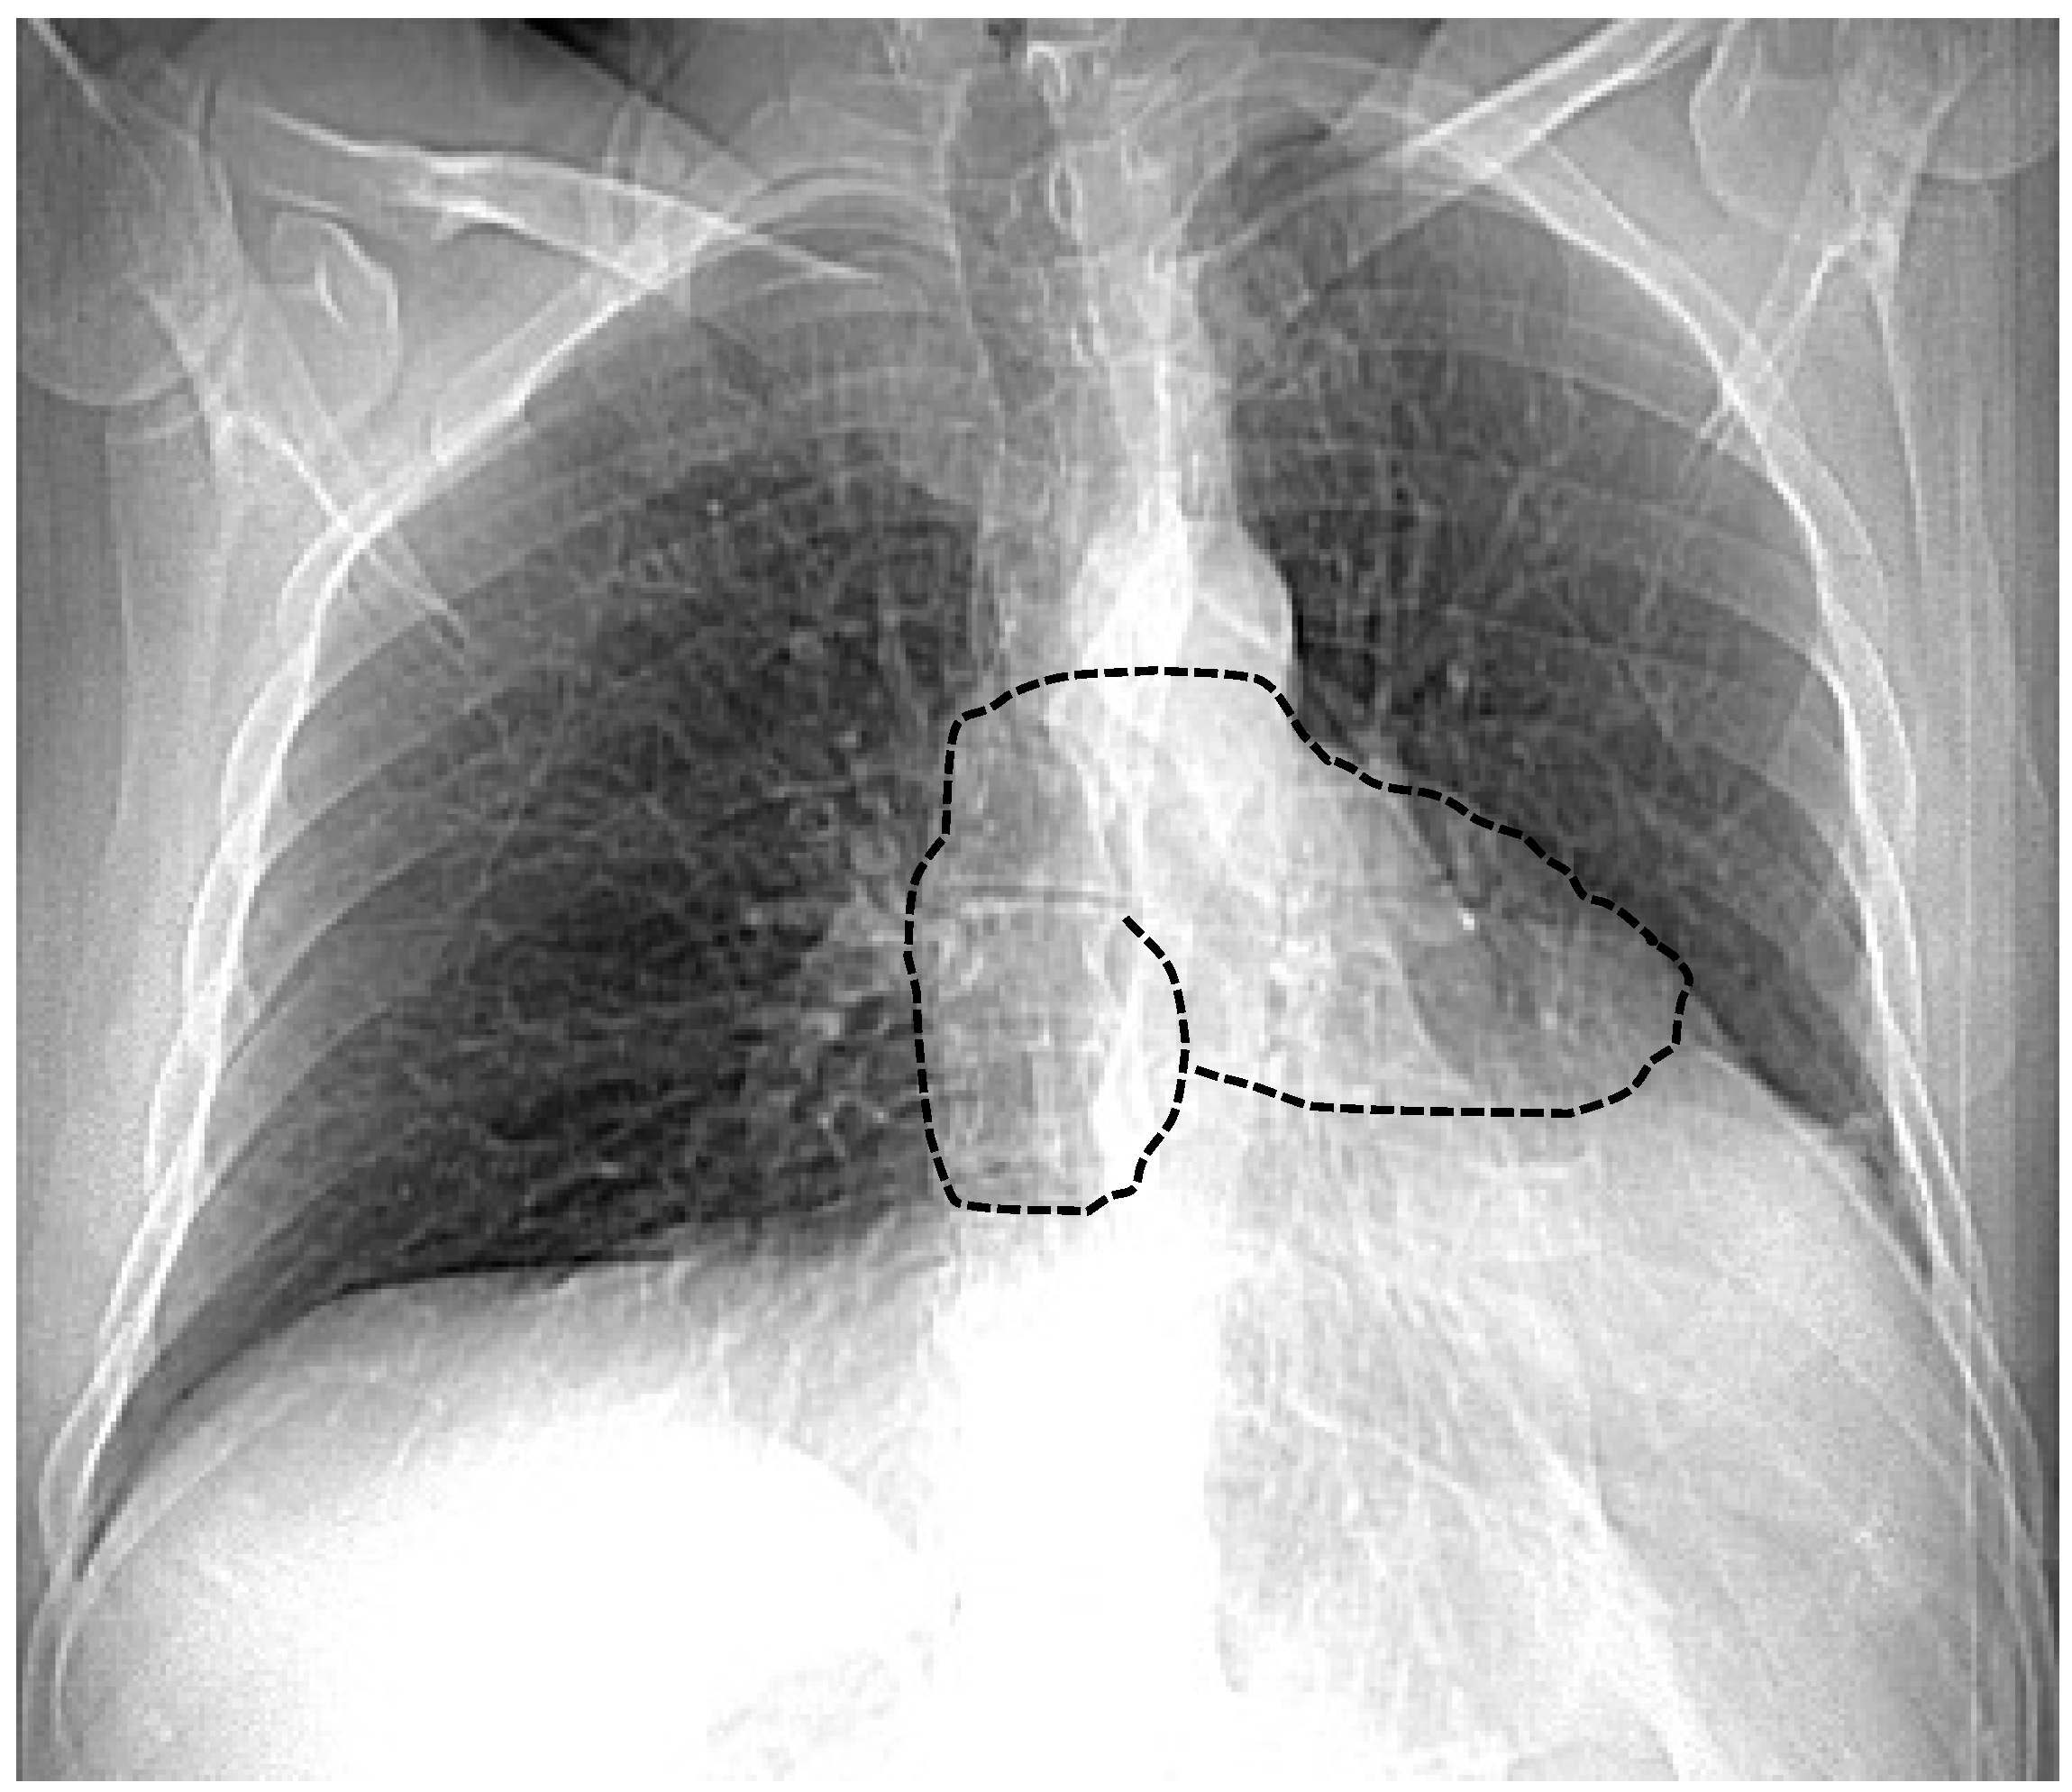

7.1. Chest X-ray

| Chest X-ray | Leftward heart displacement (Snoopy sign) Prominent main pulmonary artery Radiolucency between the heart and diaphragm | Availability Low cost Bed-side evaluation | Low sensibility Low specificity |